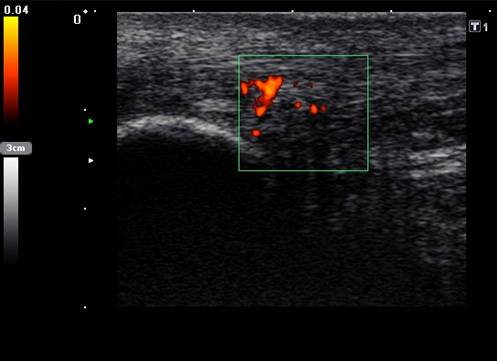

Die Farb-Doppler-Sonographie wurde 2001 erstmalig von Ohberg und Alfredson in Umea in Schweden bei schmerzhaften Achillessehnen eingesetzt 17. Bei 21 symptomatischen Sehnen konnten intratendionös mit Hilfe der Farb-Doppler-Sonographie pathologische Blutgefäße als Neovaskularisation nachgewiesen werden, die sich bei Achilles-gesunden Kontrollgruppe nicht fanden. Wenig später berichtete dieselbe Arbeitsgruppe über die erfolgreiche Farb-Doppler-kontrollierte Sklerosierung der Neogefäße mit Polidocanol 18.

2001 verglich Richards et al. die Power-Doppler-Sonographie bei symptomatischen Achillessehnenbeschwerden mit der Magnetresonanztomographie 19. Die Neogefäße in der Power-Doppler-Sonographie korrelierten mit Signalveränderungen in den T2-gewichteten MRT-Sequenzen. Aufgrund der guten Reproduzierbarkeit und Verfügbarkeit hat sich die Power-Doppler-Sonographie inzwischen bei der Darstellung der kleinen Neogefäße mit ihrem langsamen Blutfluss etabliert 202122. Die Neogefäße dringen von ventral in die Achillessehne ein. Typischerweise sind diese Neogefäße erst ab einem Sehnendurchmesser von >6,5mm nachweisbar. Bei erfolgreich behandelter Achillestendinopathie kann nach einem Jahr ein Rückgang der Anzahl der Neogefäße in der Power-Doppler-Sonographie, eine Durchmesserreduktion sowie eine Normalisierung der MRT-Signalalteration beobachtet werden 23. In einer Fallstudie konnte ein Abfall des Neovaskularisationsvolumens bei einem Patienten mit mid-portion Achillestendinopathie von 463mm3 auf 117mm3 belegt werden 24. Dies ging mit einer Verbesserung des Schmerzes in der visuellen Analogskala (von 8 auf 0) und des VISA-Scores (von 2 auf 92) einher.

634 asymptomatische Marathonläufer wurden mit der hochauflösenden Power-Doppler-Sonographie (12MHz) anlässlich von 23 Marathonveranstaltungen und 6 und 12 Monate im Anschluss untersucht 25. Mit einer odds ratio von 6.9 (p<0,001) konnte eine Neovaskularisation bei asymptomatischen Läufern die Entwicklung einer midportion Achillestendinopathie anzeigen. Eine positive Vorgeschichte für Achillessehnenbeschwerden hatte eine odds ratio von 3,8 und stellt damit ebenfalls einen ernst zu nehmenden Risikofaktor für weitere Beschwerden dar.